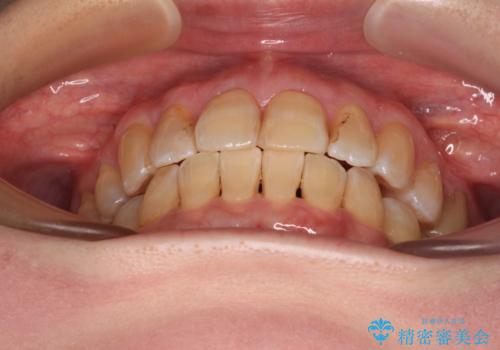

- 口元の突出感を気にして来院された患者様です。

上下前歯が著しく前突している状態であったので、上下左右の小臼歯4本を抜歯し、ワイヤー装置にて矯正治療を行うこととしました。

抜歯する第二小臼歯の後方の歯は神経近くにまで及ぶむし歯があったため、事前に処置をしておき、矯正治療後にオールセラミッククラウンにて補綴治療を行うこととしました。

第二小臼歯抜歯はイレギュラーな治療となるため、アンカースクリューを補助的に使用して、スムーズに治療を行えるように工夫をしました。